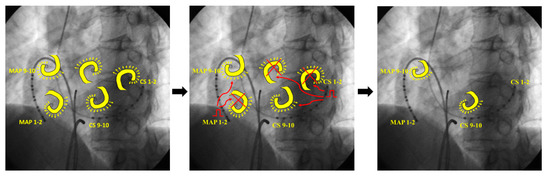

3.2.3. Case 3: 67-Year-Old Man with Symptomatic PAF